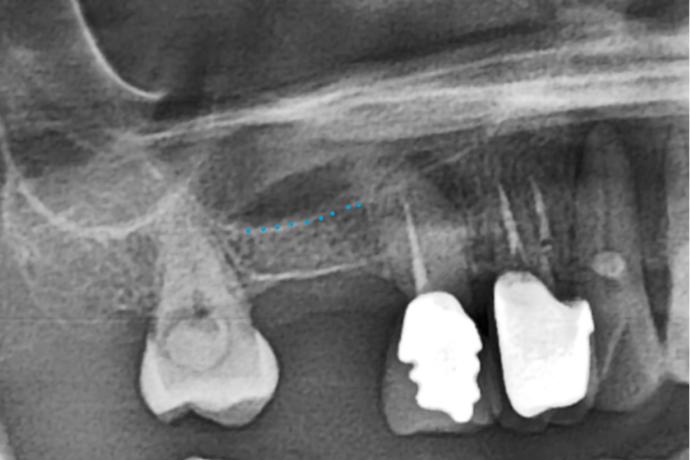

右上第一大臼齒缺牙骨頭高度明顯不足約3mm(如藍色虛線)